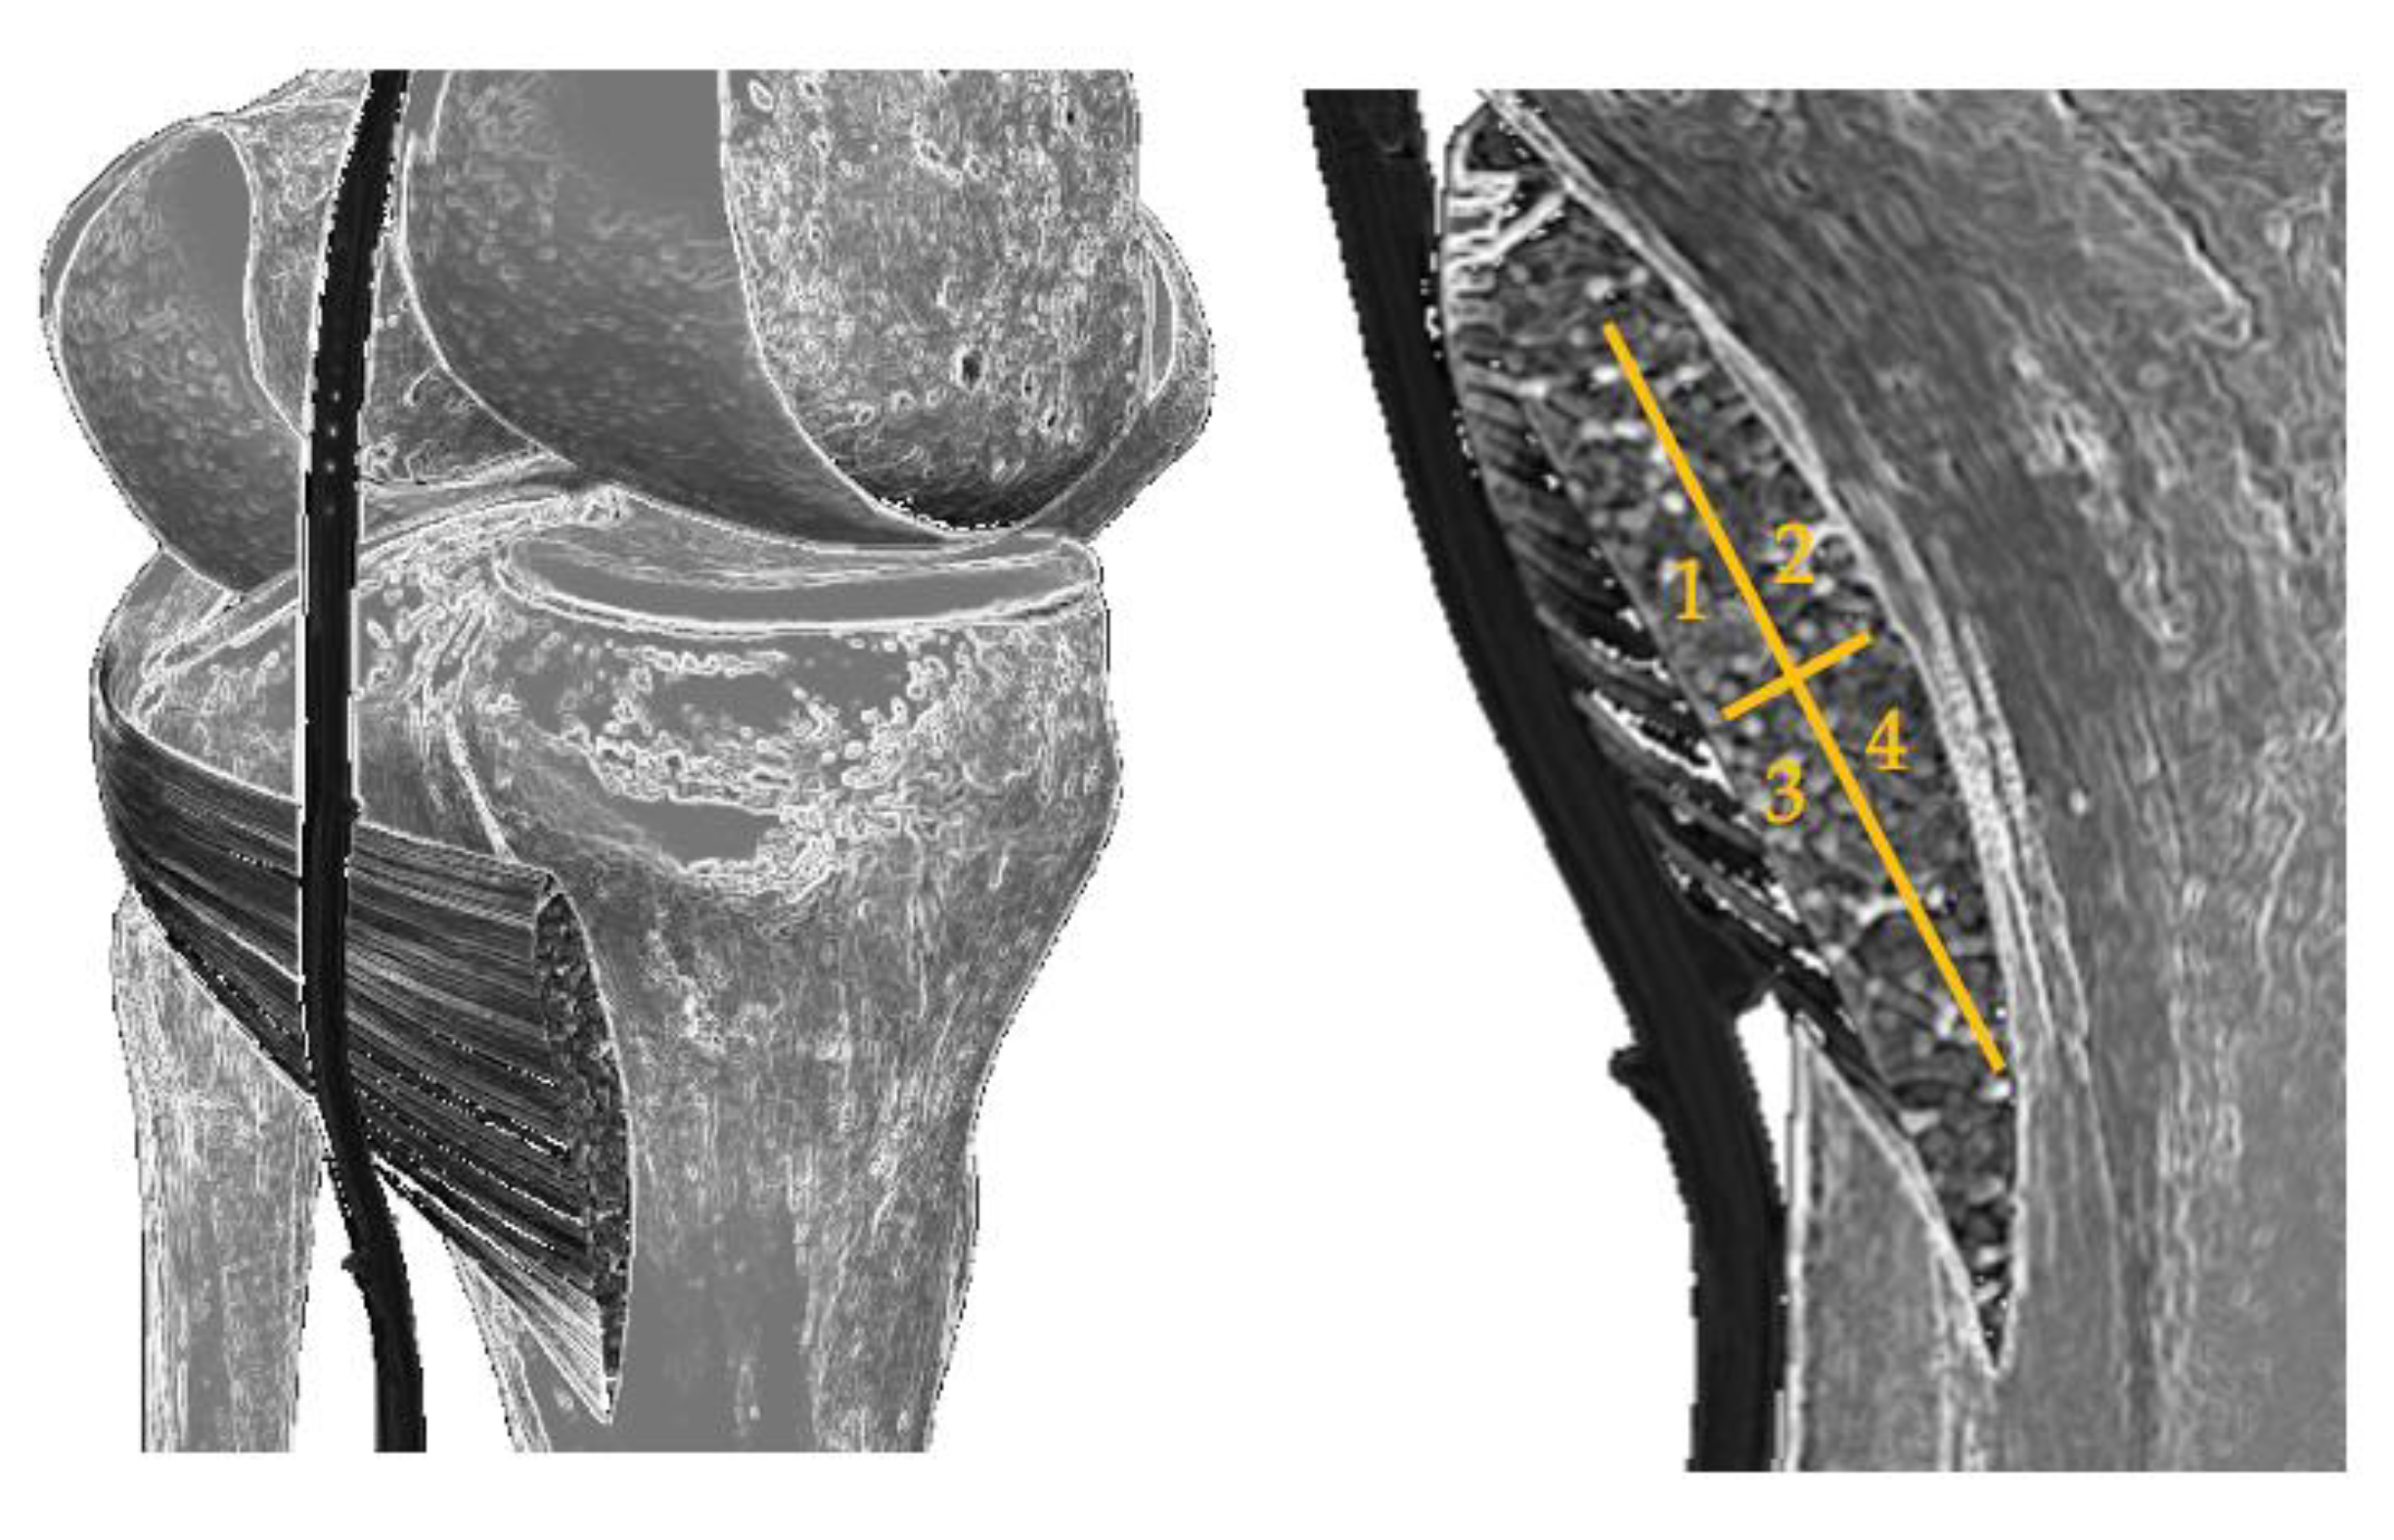

For the analysis of the most reached region of the muscle and its possible relationship with the perceived pain by Verbal Numerical Scale (VNS), a diagram of the popliteus was made and was divided into four quadrants: internal superior (most medial side, closest to the point of access with the needle), external superior (most lateral side), internal inferior and external inferior (Figure 1).

Figure 1.

Diagram of the division of the popliteus into four quadrants.